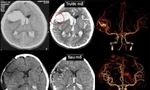

Trao đổi với phóng viên về đánh giá dành cho y tế Việt Nam, GS Pereira đặc biệt nhấn mạnh ba yếu tố. Thứ nhất là tốc độ phát triển vượt bậc của các trung tâm can thiệp, thể hiện qua hạ tầng được đầu tư bài bản và số lượng bác sĩ được đào tạo tăng nhanh trong những năm gần đây. Thứ hai là khả năng hội nhập quốc tế. Các bác sĩ trẻ của Việt Nam tham gia trao đổi, thảo luận bằng tiếng Anh khá tự tin, điều mà trước đây chưa phổ biến. Thứ ba là dấu ấn thực chất qua những ca bệnh phức tạp được thực hiện tại Việt Nam, trong đó có những ca từng được truyền hình trực tiếp sang Hội nghị LINNS tại Paris, cho thấy năng lực điều trị không chỉ tốt lên mà còn đủ sức chia sẻ kinh nghiệm với cộng đồng quốc tế.

linnc-1.jpg

Hàng chục báo cáo tham luận và thảo luận cụ thể trên từng ca bệnh đã diễn ra sôi động tại Hội nghị LINNS